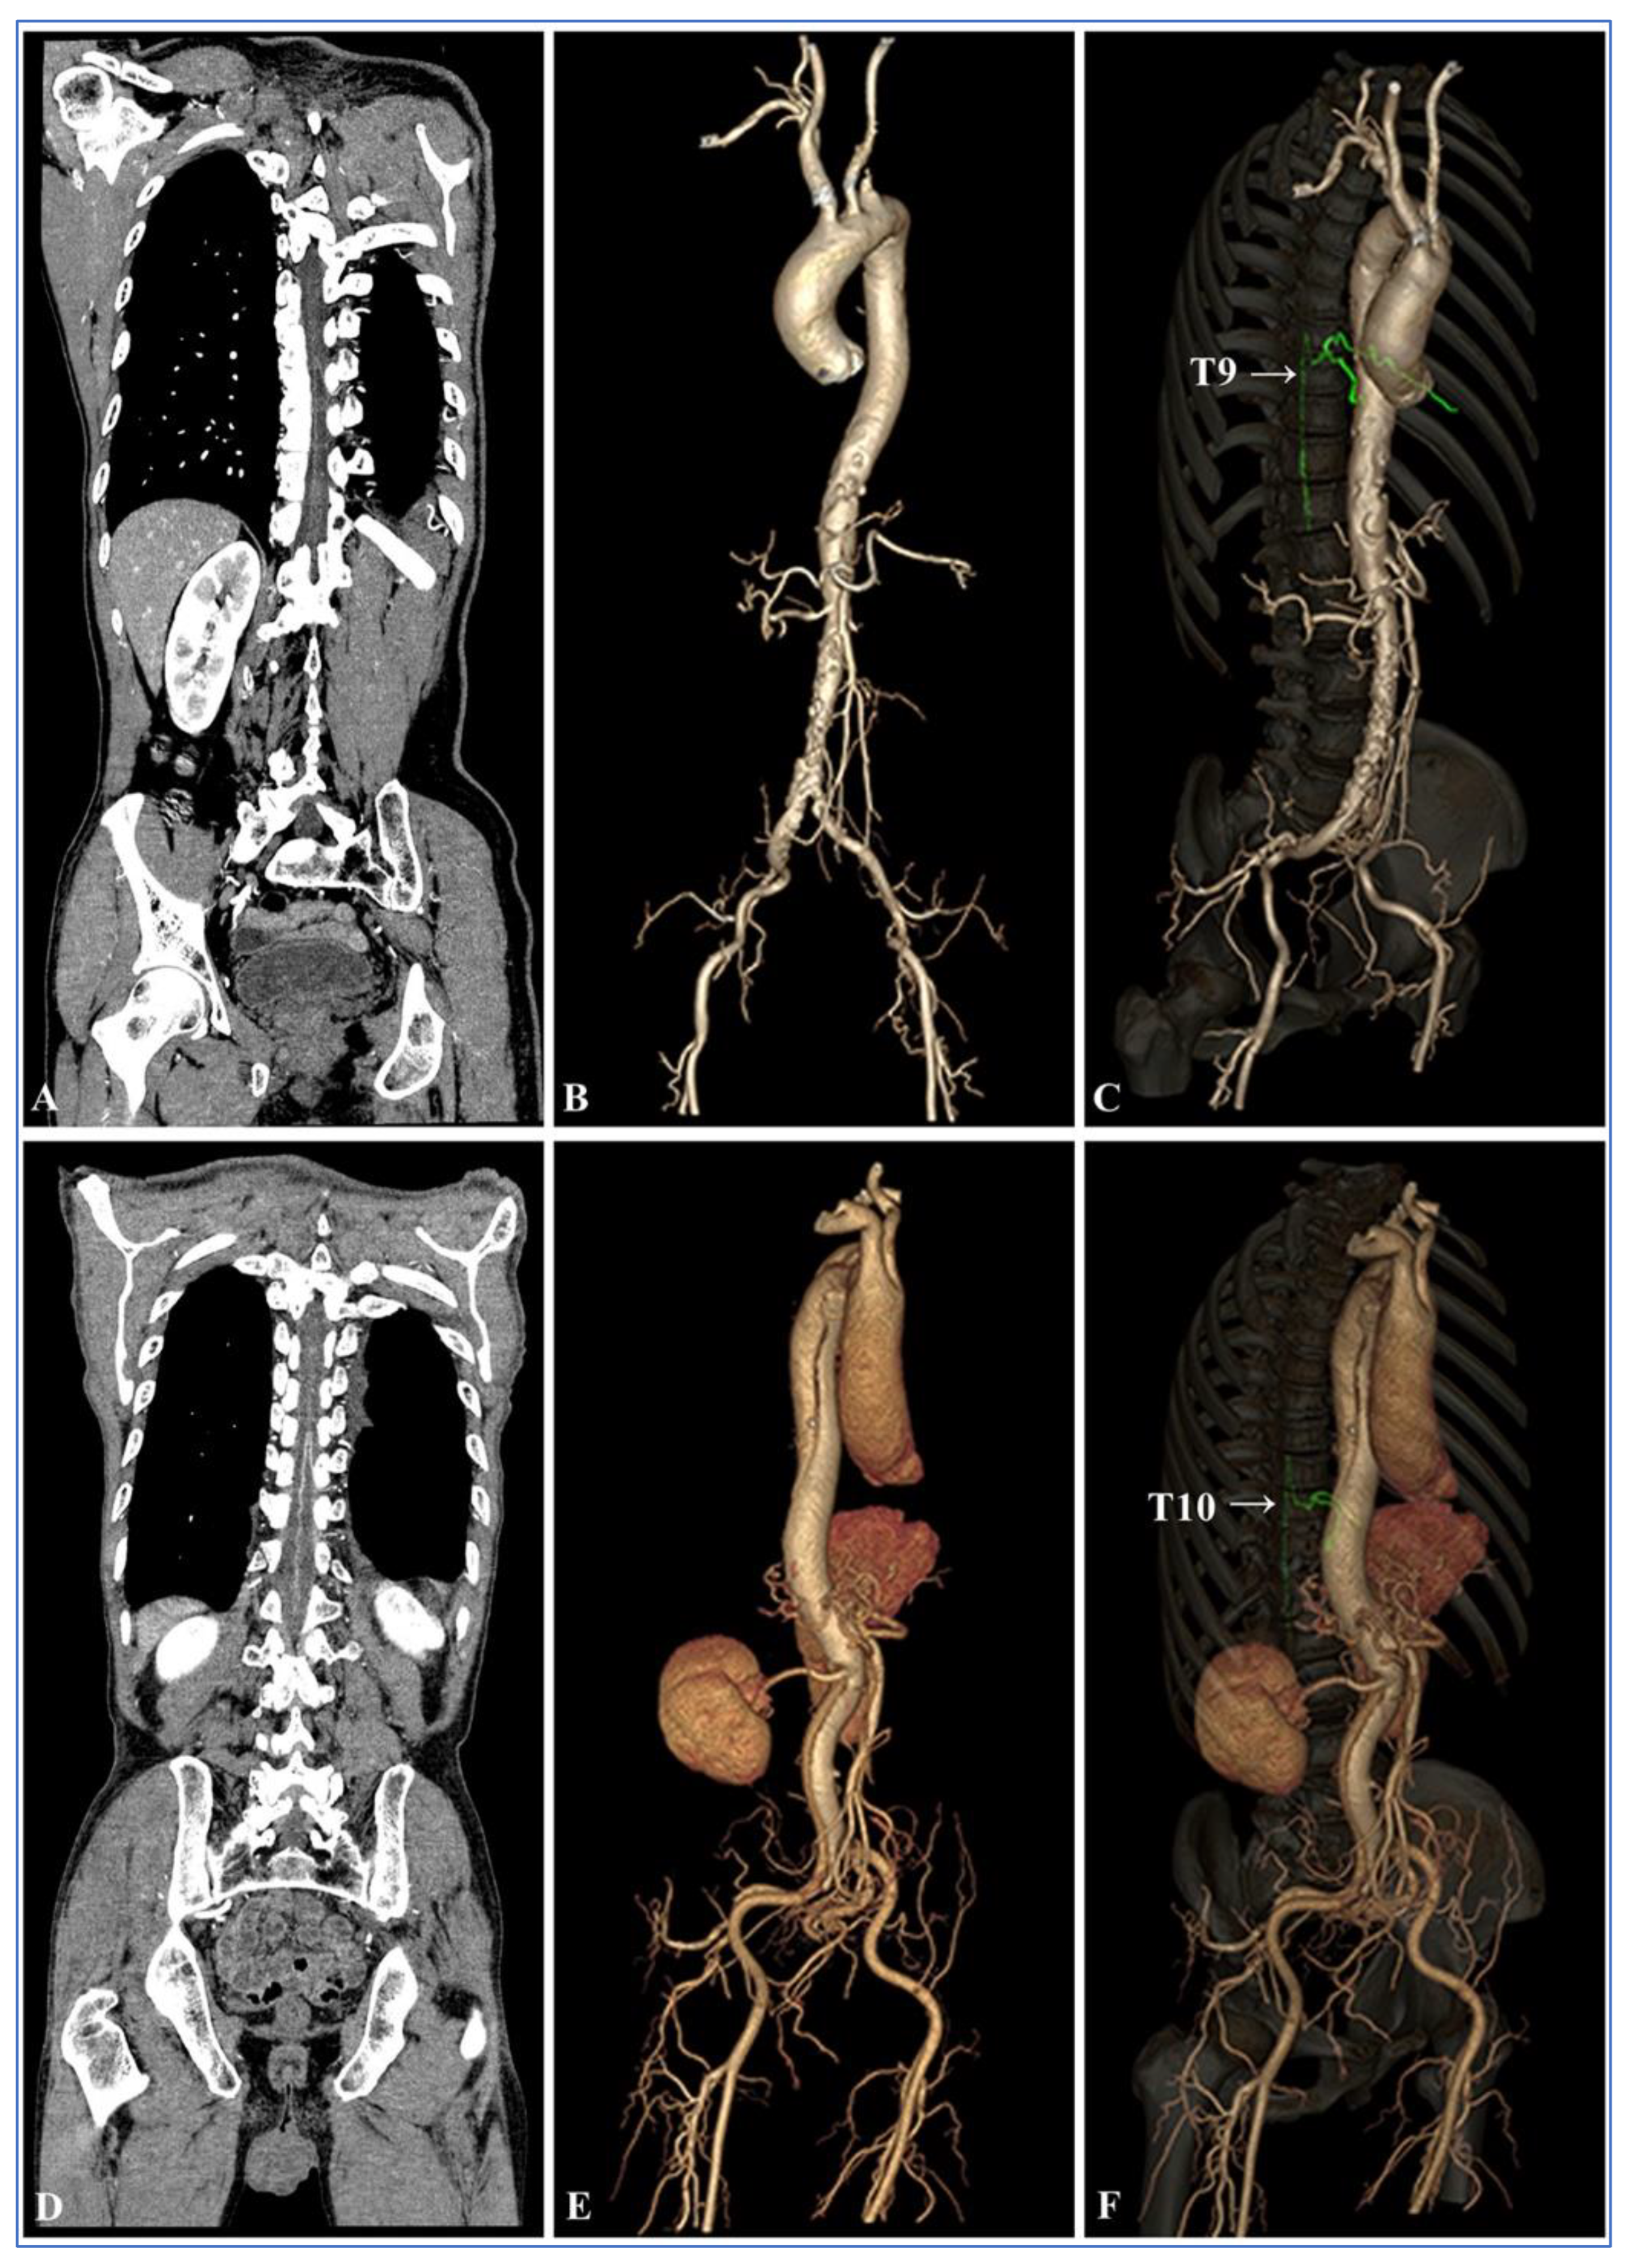

3.4. Visual Analysis of the AKA

3.5. Comprehensive Assessment